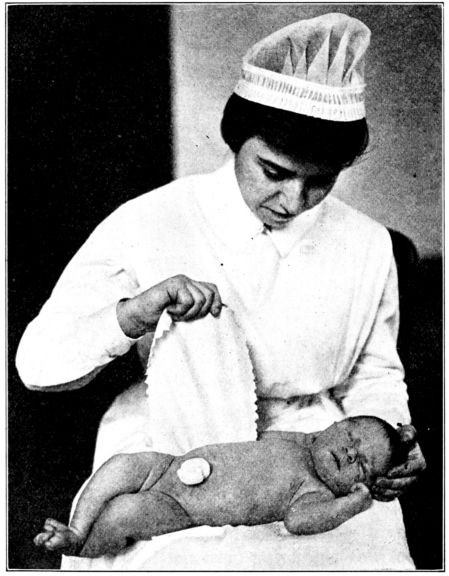

| 157. | Cord dressed with dry sterile gauze | 470 |